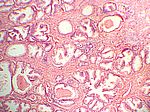

Prostatahyperplasie, HE